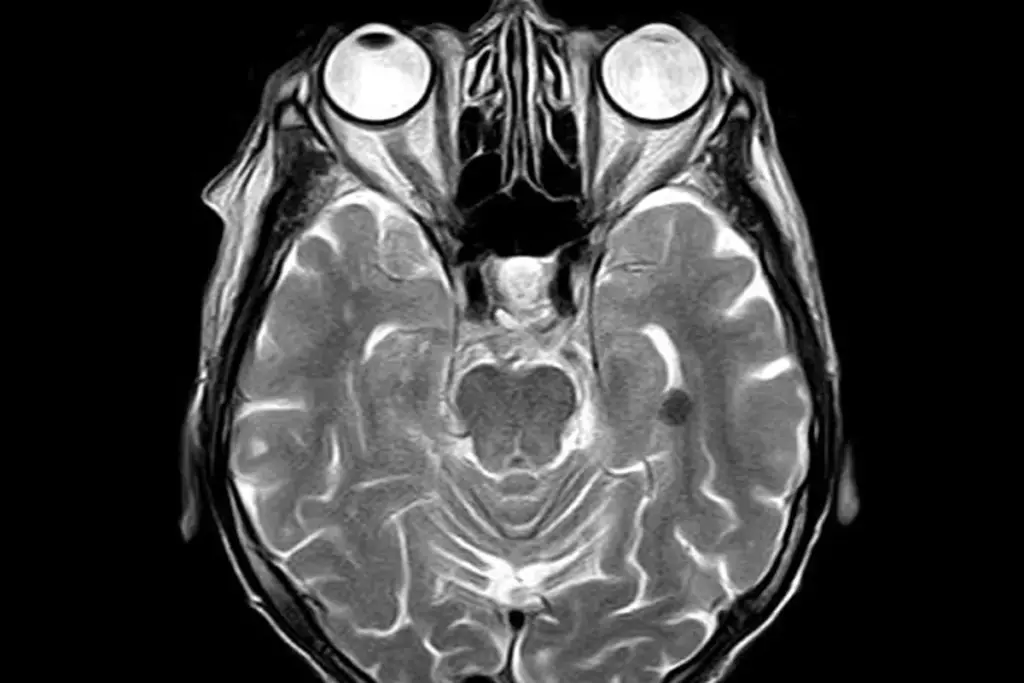

An MRI scan can show doctors the inner ear and nearby areas in great detail. This helps find out why you might be hearing these sounds. Knowing the cause helps doctors create a good treatment plan for you.

What an MRI Can Detect in Tinnitus Patients

An MRI scan can show what’s causing the ringing in your ears if tinnitus symptoms don’t go away. Tinnitus often points to a deeper health issue. An MRI can find the main cause.

Meniere’s Disease Indicators

Meniere’s disease affects the inner ear and can cause tinnitus, vertigo, and hearing loss. An MRI isn’t the first choice for diagnosing Meniere’s. But it can help rule out other conditions with similar symptoms.

Limitations of MRI for Tinnitus Diagnosis